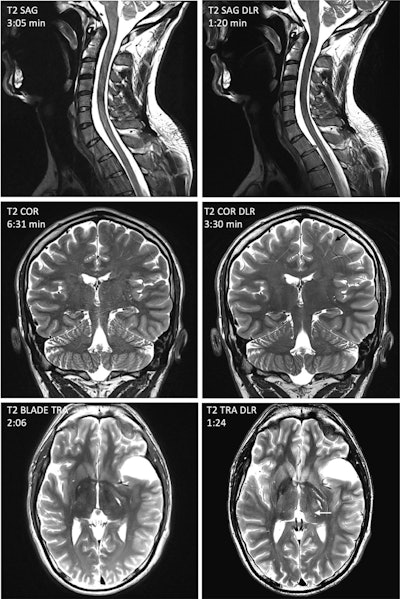

Representative artifacts frequently encountered with accelerated deep-learning reconstruction (DLR) sequences, illustrated using images from a healthy volunteer with written informed consent. (Gray arrow) Severe artifacts rendering sagittal spinal cord T2 DLR images nondiagnostic. Evaluation of the sagittal spinal cord T2 DLR images is limited by severe artifacts. (Black arrow) Linear artifacts are enhanced in coronal T2 DLR image. (White arrow) Axial brain image showing signal heterogeneity in the thalamus. In addition, there is blurring in the basal ganglia and insular region.European Journal of Radiology

However, while DLR showed excellent performance for musculoskeletal and prostate imaging in terms of quality, it had limitations in some other areas, especially neurological imaging. The researchers cautioned that DLR seems to amplify motion- and flow-related artifacts, which made it less suited for brain imaging. Additionally, the DLR used was not clinically applicable for the high-resolution 3D sequences commonly used in neurological studies. The authors also found that there was suboptimal image quality in contrast-enhanced studies; as a result, they noted that “DLR sequences have not been approved for contrast-enhanced acquisitions.”